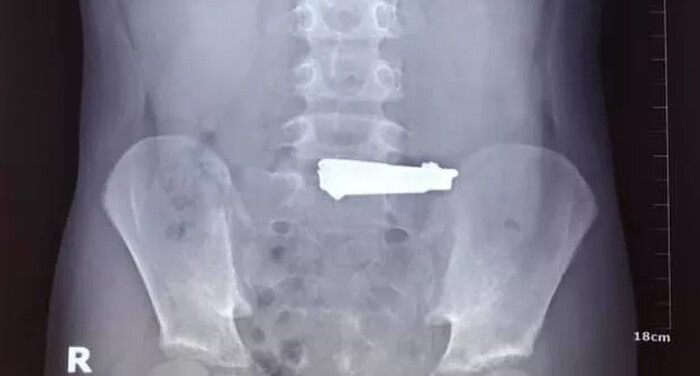

Qua thăm khám và nội soi dạ dày, các bác sĩ phát hiện dị vật là một chiếc bấm móng tay có kích thước 60x16 mm, nằm tại vị trí phình vị lẫn thức ăn, gây tổn thương xước niêm mạc dạ dày. Ngay lập tức, kíp nội soi tiêu hóa đã tiến hành gắp dị vật kịp thời và thành công.